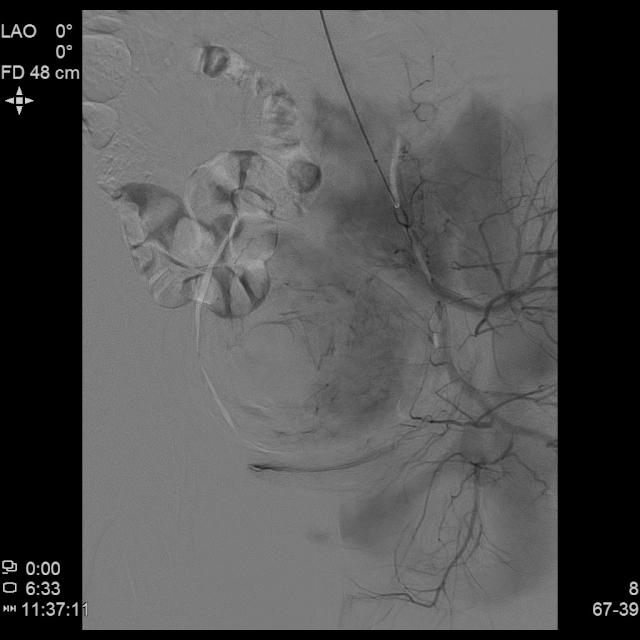

- 经桡动脉入路置入导管造影显示双侧子宫动脉明显增粗,染色丰富,子宫明显增大

- 进一步超选插管左侧子宫动脉造影确认位置